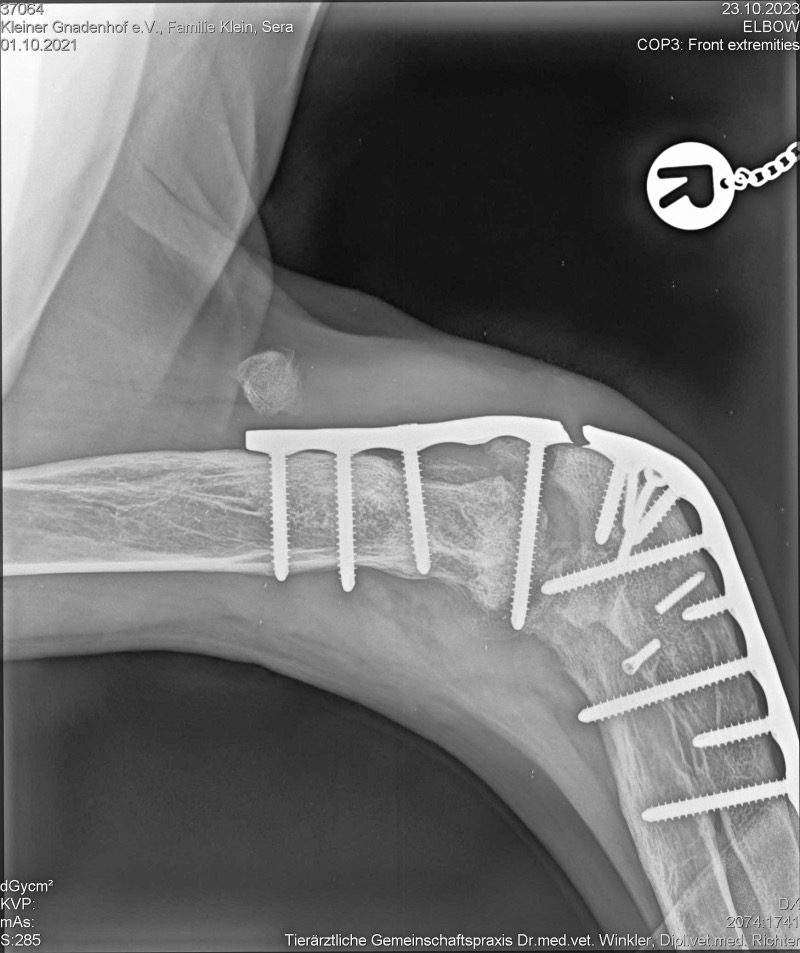

Es war für jeden zu sehen, dass Sera das Laufen große Probleme bereitete. Auch offensichtlich war, dass ihr Ellenbogengelenk immer mehr anschwoll. Eine Röntgenkontrolle wurde vorgenommen und es war zu erkennen. dass starke Veränderungen im Gelenk vorhanden waren, die die Ursache für den Bewegungsschmerz waren.

Unsere Tierarztpraxis setzte sich wieder mit dem Spezialisten Dr. Pfeil in Verbindung und gemeinsam beriet man, wie der wilden Maus geholfen werden kann. Damit ihr ein schmerzfreies Laufen möglich wird, muss eine Versteifung des Gelenks erfolgen. Dazu war die Anfertigung eines speziellen Implantates nötig. Nachdem dieses geliefert worden war, fuhren wir wieder einmal mit Sera im „Gepäck“ Richtung Dresden. Auch wenn wir immer sehr zuversichtlich zu solchen Terminen gefahren waren, so machten wir uns doch gerade jetzt, wo unser Liebling Jay nach einer OP erlöst werden musste, große Sorgen.

Wir konnten erst aufatmen, als wir die Nachricht erhielten, dass es der Großen gut geht und sie alles gut überstanden hat. Nach drei Tagen stationären Aufenthalt durfte Sera wieder in ihr Taxi nach Letschow steigen.

Das ganze Ausmaß des Desasters zeigte sich während der schwierigen und langen Operation. Das eingesetzte Implantat musste entfernt werden, da Elle und Speiche bereits zusammengewachsen waren. Eine der vielen Schrauben befand sich im Gelenk des Beines, wodurch auch die Schmerzen verursacht wurden. Eine weitere Schraube war derart eingewachsen, dass eine Entfernung nicht mehr möglich war. Sie hielt die zusammengewachsenen Knochen zusammen und musste durchtrennt werden, damit wieder Bewegungsfreiheit zwischen den Knochen entsteht.